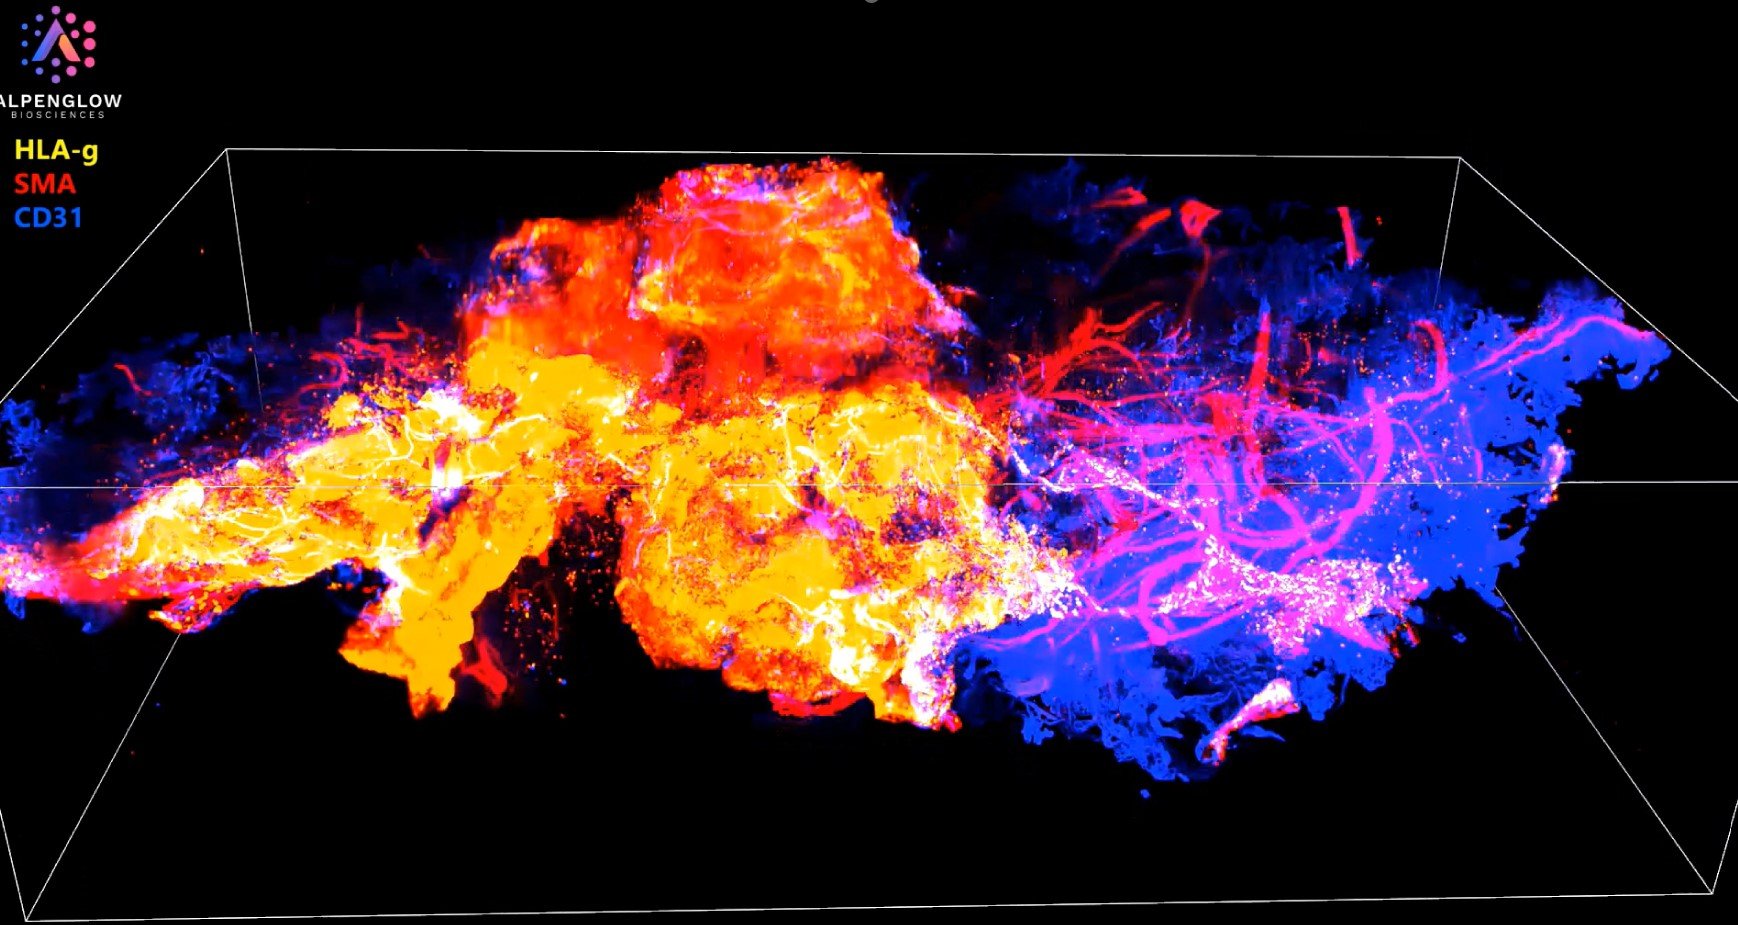

Exploring Human Placenta in 3D: A New Era in Spatial Biology

Experience the intricate architecture of human placenta tissue in this captivating 3D video, designed to showcase the power of advanced spatial biology.